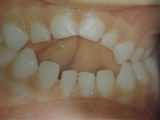

Ανωμαλίες αριθμού, θέσης και σχήματος νεογιλών και μονίμων δοντιών

Υπάρχουν διάφορες καταστάσεις που χρήζουν διάγνωσης και θεραπείας από τον παιδοδοντίατρο. Δείτε τις μία προς μία κάνοντας κλικ στις παρακάτω εικόνες.